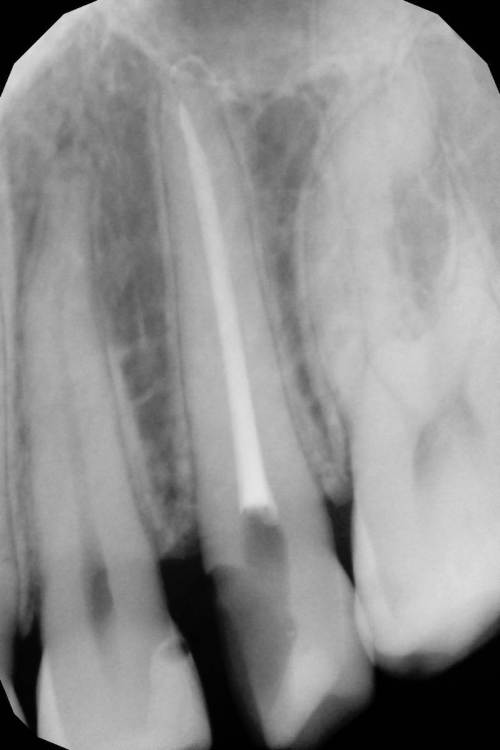

Как часто мы сталкиваемся с такими процессами и как редко пациент сам предъявляет какие то жалобы на такие зубы. Максимум это… застревание пищи.

Глубина полости ниже уровня десневого края на 2-3 мм. Коагуляция, ENDO, анатомичный билдап, проверка качества реставрации и отсутсвие нависающего края (интерпроксимальный снимок), рекомендации.

На следующий день никаких жалоб.

Доступ проводился шаровидным бором, синим финиром и аналогом бора endo z.

Эндо 25.06, 40.04, 60.02. Обтурация инжекторной техникой. Восстановление гармонайз а3 и желтая текучка от эстелайта (говорят ее сняли с производства, жаль, очень классный материал был)